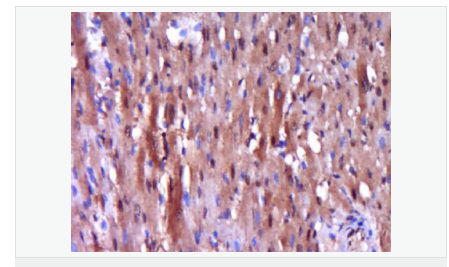

| 產(chǎn)品應(yīng)用 | WB=1:500-2000 ELISA=1:5000-10000 IHC-P=1:100-500 IHC-F=1:100-500 Flow-Cyt=1ug/Test ICC=1:100 IF=1:100-500 (石蠟切片需做抗原修復(fù)) not yet tested in other applications. optimal dilutions/concentrations should be determined by the end user. |

| 產(chǎn)品介紹 | Caspase 9 (also known as ICE like apoptotic protease 6 (ICE LAP6), apoptotic protease Mch6, and apoptotic protease activating factor 3 (Apaf3)) is a member of the peptidase family C14 that contains a CARD domain. This caspase is active as a heterotetramer and has been reported to have two isoforms. ProCaspase 9 has been reported to be approximately 47 kD. This caspase is present in the cytosol and, upon activation, translocates to the mitochondria. Caspase 9 is involved in the caspase activation cascade responsible for apoptosis execution and cleaves/activates Caspase 3 and Caspase 6. Caspase 9 is inhibited by the dominant negative isoform, BclXL, cIAP1, cIAP2, XIAP, and Livin. This caspase becomes activated when recruited to Apaf1/cytochrome c complex, and following cleavage by Apaf1, granzyme B, Caspase 3, possibly Caspase 8 and Caspase 10 into large p37 and small p10 subunits. Caspase 9 intereacts with BIRC7 and has been shown to cleave PARP and vimentin. Function: Involved in the activation cascade of caspases responsible for apoptosis execution. Binding of caspase-9 to Apaf-1 leads to activation of the protease which then cleaves and activates caspase-3. Proteolytically cleaves poly(ADP-ribose) polymerase (PARP). Isoform 2 lacks activity is an dominant-negative inhibitor of caspase-9. Subunit: Heterotetramer that consists of two anti-parallel arranged heterodimers, each one formed by a 35 kDa (p35) and a 10 kDa (p10) subunit. Caspase-9 and APAF1 bind to each other via their respective NH2-terminal CED-3 homologous domains in the presence of cytochrome C and ATP. Interacts (inactive form) with EFHD2. Interacts with HAX1. Interacts with BIRC2/c-IAP1, XIAP/BIRC4, BIRC5/survivin, BIRC6/bruce and BIRC7/livin. Tissue Specificity: Ubiquitous, with highest expression in the heart, moderate expression in liver, skeletal muscle, and pancreas. Low levels in all other tissues. Within the heart, specifically expressed in myocytes. Post-translational modifications: Cleavages at Asp-315 by granzyme B and at Asp-330 by caspase-3 generate the two active subunits. Caspase-8 and -10 can also be involved in these processing events. Phosphorylated at Thr-125 by MAPK1/ERK2. Phosphorylation at Thr-125 is sufficient to block caspase-9 processing and subsequent caspase-3 activation. Similarity: Belongs to the peptidase C14A family. Contains 1 CARD domain. SWISS: P55211 Gene ID: 842 Database links: Entrez Gene: 842 Human Entrez Gene: 12371 Mouse Omim: 602234 Human SwissProt: P55211 Human SwissProt: Q4FJK5 Mouse Unigene: 329502 Human Unigene: 88829 Mouse Unigene: 32199 Rat Important Note: This product as supplied is intended for research use only, not for use in human, therapeutic or diagnostic applications. Caspase-9半胱氨酸蛋白酶家族成員之一,又稱ICE-Lap6(ICE Like apoptotease 6)參與細胞凋亡過程和細胞因子的加工過程,在許多胚胎和成人組織中都有分布。此抗體主要用于腫瘤研究。 |